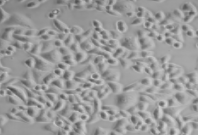

A2780/DDP顺铂耐药株细胞培养常见问题分析以下细胞处理方法及细胞说明书仅供参考,具体操作还需要根据到货时细胞密度,细胞生长状态等具体情况,酌情处理,如需要更详细技术指导,请及时电话或邮件联系。

肉眼观察细胞培养基颜色,显微镜观察细胞生长情况,并对细胞进行不同倍数拍照(建议收到时的培养瓶拍一张照片,显微镜拍收到时的细胞100X,200X各一张)。

显微镜观察细胞,当细胞融汇至80%左右(可以传代的情况下),细胞应该在37度培养箱预温1-2h后再做处理。如未达到细胞传代密度,培养瓶应预留一部分培养基继续培养。